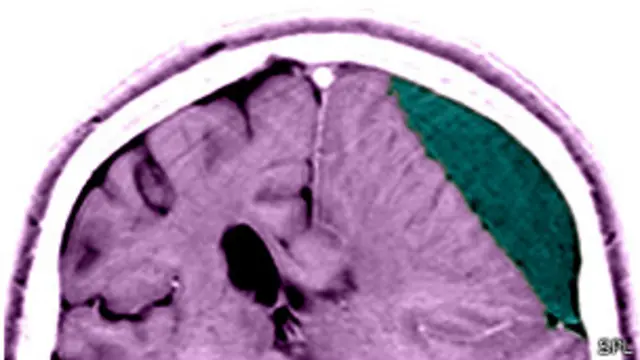

Las lesiones en la cabeza pueden dejar a las víctimas susceptibles a una muerte temprana, incluso años después, a causa de déficits de razonamiento. Esta es la conclusión de un estudio a gran escala realizado en sobrevivientes a golpes fuertes en la cabeza.

Se cree que la lesión causa un daño permanente en las redes neuronales del cerebro y pueden alterar el juicio de las personas y sus habilidades para lidiar con situaciones nuevas.